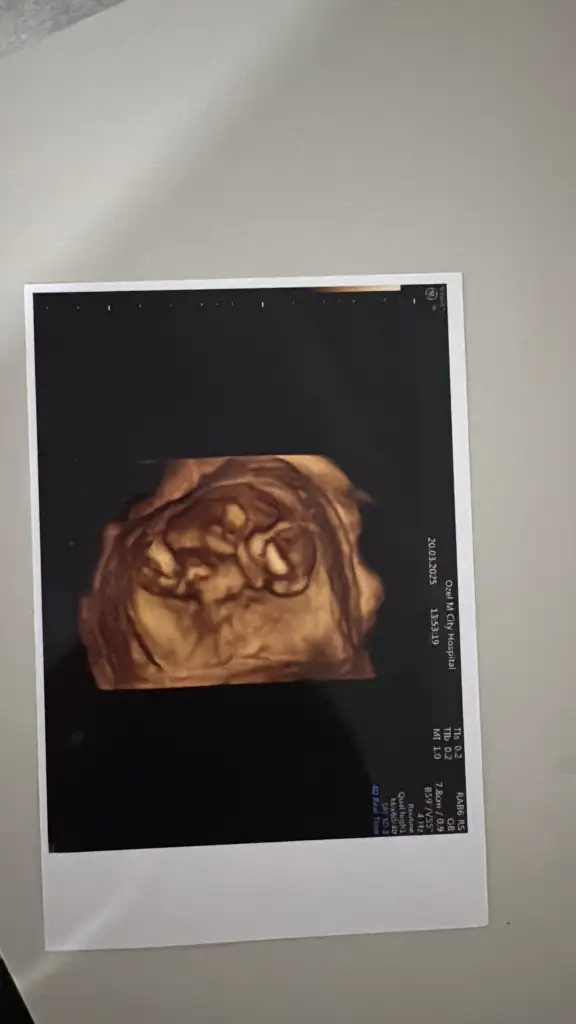

benimkine de yorum yapar mısınızz çok meraktayım en son 12.haftada gittik şu an 14+2 deyizNub teorisine göre erkek

3d görüntü ile tahmin yapamıyorumbenimkine de yorum yapar mısınızz çok meraktayım en son 12.haftada gittik şu an 14+2 deyiz

başka görüntüler var ama evde değilim çekemedim teşekkür ederim3d görüntü ile tahmin yapamıyorum